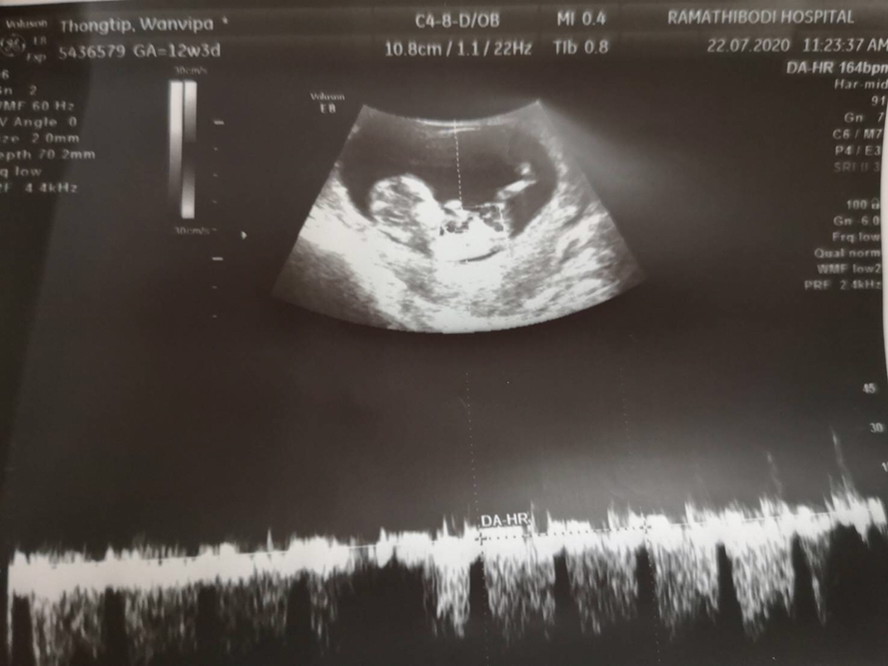

เค้าซาวด์ตอน 12w 3d เห็นน้องครบแล้วค่ะ กราฟเส้นๆ ข้างล่างคืออัตราการเต้นหัวใจน้องค่ะ